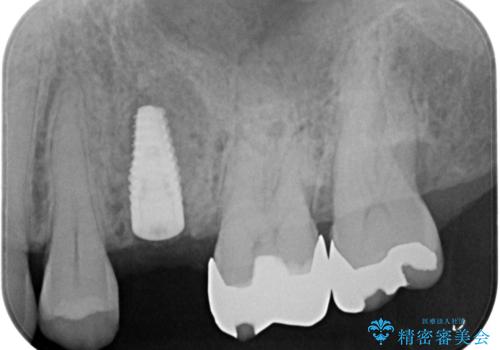

歯茎が腫れる インプラントでの治療

- 40代女性

- 10ヶ月

- 5-10回

- 左上5/インプラント:242,000円 骨増生:55,000円 カスタムアバットメント:110,000円 インプラント用仮歯:22,000円 ジルコニアクラウン:121,000円 合計550,000円費用は治療当時の料金となります